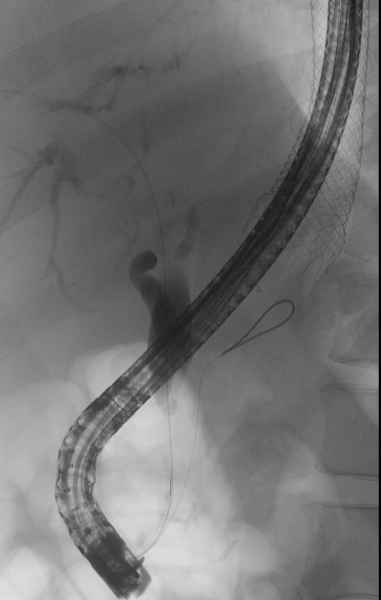

EDGE procedure: esophageal stent to the rescue

Vídeo